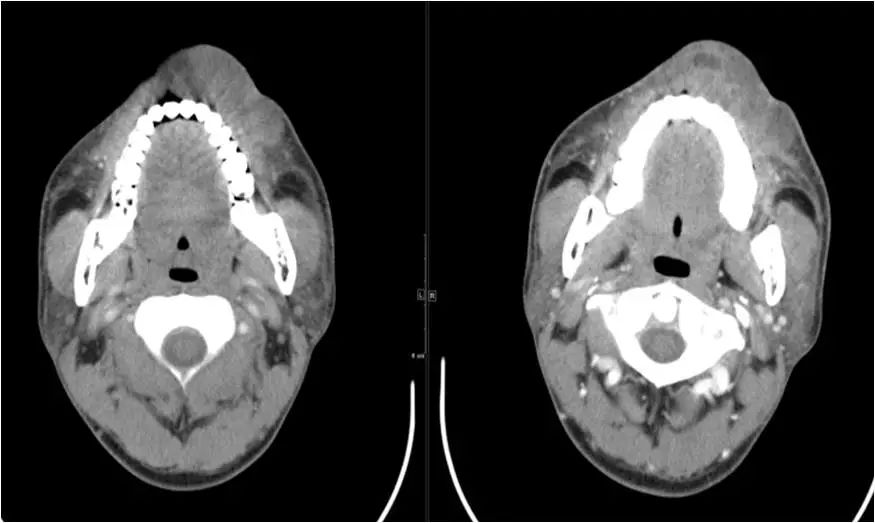

04 咀嚼肌间隙、颌下间隙、左侧颞下间隙,颊间隙,翼颌间隙

男,55岁,左下后牙反复肿疼1年余,加重1月余,疼痛剧烈伴张口受限,面部肿胀。

咀嚼肌间隙有脓肿形成。